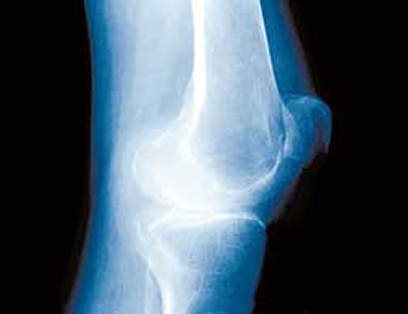

התסמינים העיקריים של שחיקת הסחוס במפרק הברך הם כאבים המתגברים בעיקר בעליה ובירידה במדרגות וכאב בעמידה ממושכת. לעיתים מופיעים הכאבים גם בלילה ועם התקדמות השחיקה מופיעה גם נפיחות ונוזל בתוך פרקי הברך. בשלב זה הכאבים מלווים גם בהגבלה בתנועות, קושי בדריכה ובהליכה.

ברך עם שחיקת סחוס. כאבים עזים בעלייה וירידה במדרגות